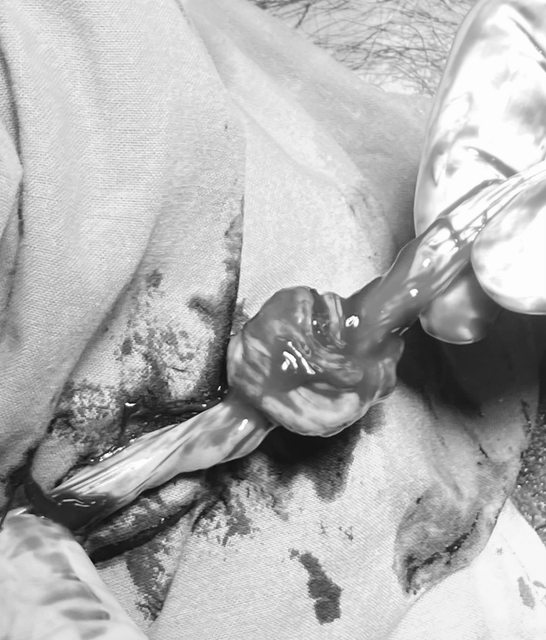

這就是傳說中的臍帶死結(已黑白處理,但還是慎入)

比預期重量多了500g, 同時還發現臍帶打了死結.(你真的很皮喔...臭小子XD)

詹副院長說臍帶打死結, 還能順利自然產, 你兒子一定是天選之人. (因為他說大部分 臍帶死結都會掉胎心音, 然後緊急剖腹)